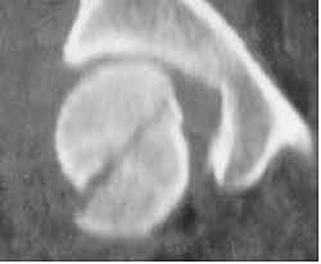

Fractura

Jefferson

Fractura Jefferson Fragmente

osoase la stanga apofizei odontoide

Fractura Jefferson Fractura spanzuratului

Aspect CT